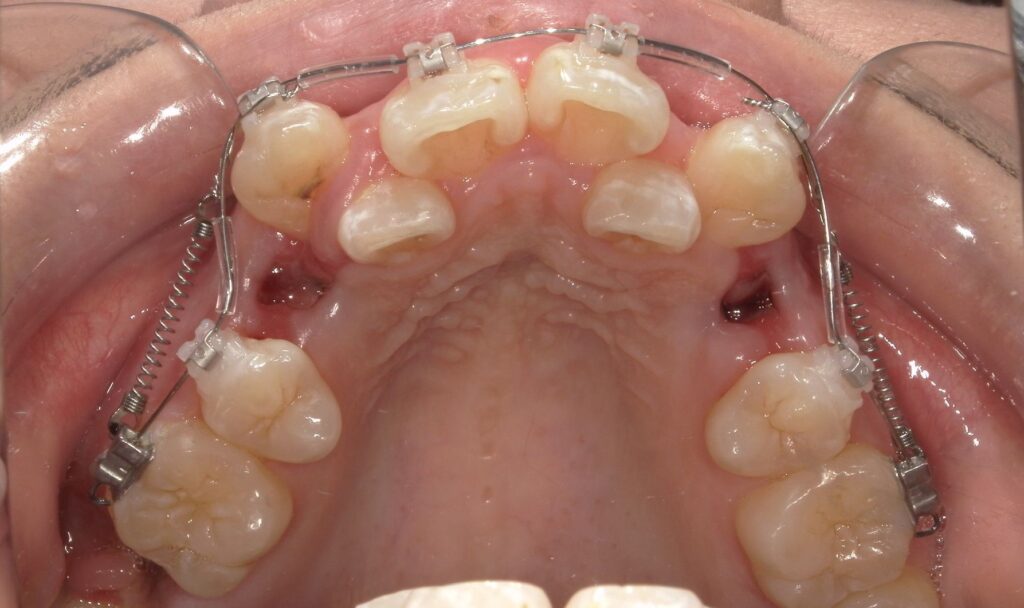

【治療開始前】八重歯の矯正を始める前の歯並び

初診時の写真からも分かるように、前歯に強い叢生(ガタガタ)があり、笑ったときに歯並びの乱れが目立つ状態でした。